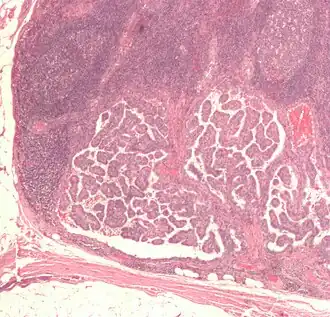

В зависимости от гистопатологического строения, классифицируют как папиллярный, фолликулярный, медуллярный и анапластический.[3] Наиболее часты папиллярные и фолликулярные карциномы. Фолликулярный и папиллярный раки щитовидной железы относят к высокодифференцированным формам. При выявлении этих типов карцином на ранних стадиях прогноз благоприятный до 90 % случаев.

Раки щитовидной железы классифицируют согласно их патогистологическим характеристикам.[13][14] Различают следующие варианты (частота встречаемости разных подтипов может показывать местную вариацию):

- Папиллярный рак щитовидной железы до 75 %

- Фолликулярный рак щитовидной железы до 15 %

Фолликулярный и папиллярный типы классифицируют как «высокодифференцированный рак щитовидной железы».[16] Эти типы имеют более благоприятный прогноз, чем медуллярный и недифференцированные типы.[17]